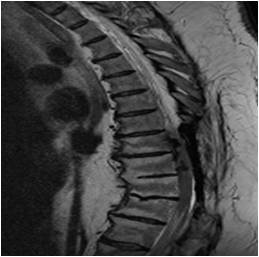

Idiopathic Hypertrophic Pachymeningitis

A chronic progressive diffuse inflammatory fibrosis of the dura mater. Diagnosis of exclusion since meningioma, lymphoma, sarcoid and TBc can present in a similar fashion. MRI findings of low signal intensity mass extending over several levels with linear or nodular peripheral enhancement (representing active inflammation) highly suggestive of the diagnosis. [ Article ]

chronic myelopathy with several decompressions

Courtesy Jay A Kaiser MD